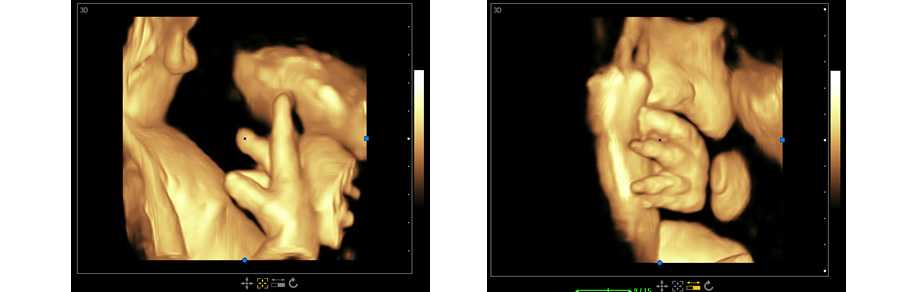

立體光源成像 胎兒容貌實時顯示